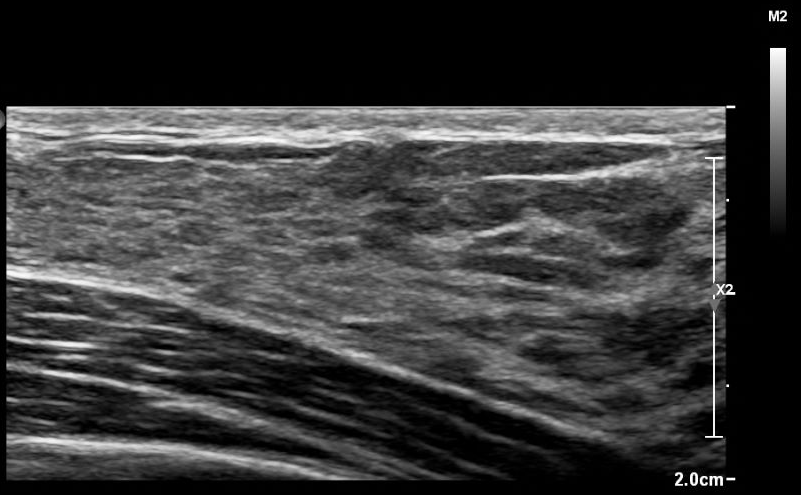

The waiting room was small, lit like a clinic in a hospital. It smelled like a perfume I tried in a store while visiting my family in Japan a few years back that was supposed to smell like spinal fluid. I don’t know why I sprayed it on my wrist, the smell made me sick for the rest of the day even after I tried to scrub it off. Who would ever want to smell like that? A few people had been called back before me now, elderly wives shuffled back to the examination rooms with their husbands. A lot of the chatter had died down. Quiet rooms are the worst for me, all I can focus on is the sound of my own heart beating. It sounds sick, like it’s whining with every contraction. Is it really that fast? Anyone that had seen me for the past month must have thought I accidentally superglued my two fingers to my carotid artery. It’s such an awful sound. Highway pileup with 160 new cars crashing into it every minute. I wish everyone could hear this when I walked into a room. Your period’s so loud! haahhhh. Bear down, breathe through pursed lips. That’s what slows it down. I can’t stand it… The gabapentin stops my chest from hurting, but I can still feel it buzzing where it would hurt, I can hear that it hurts. When I eventually have a heart attack, I’m sure I’ll hear it before I feel it. I imagined the sound of a shipping crate being torn in half and then me dying. I’m going to have an echocardiogram later, maybe they’ll catch that sound on the speakers.

I couldn’t help but laugh during my echo, hearing my heartbeat doubled on the speakers made me feel like I was losing my mind. It was painfully long and my chest was sore from how hard the nurse was pushing the probe into me. I was waiting on a bench outside the hospital for my mom to finish some errands she had been running down the street. The sun was shining directly on me, it made me feel woozy but I didn’t want to go back inside. The heat was drying the ECG gel into an awful sticky consistency all over my chest. My shirt kept getting glued to the spot where they spread the gel, I pulled at it and it made a noise as it came unstuck. I listened to birds and my heart.